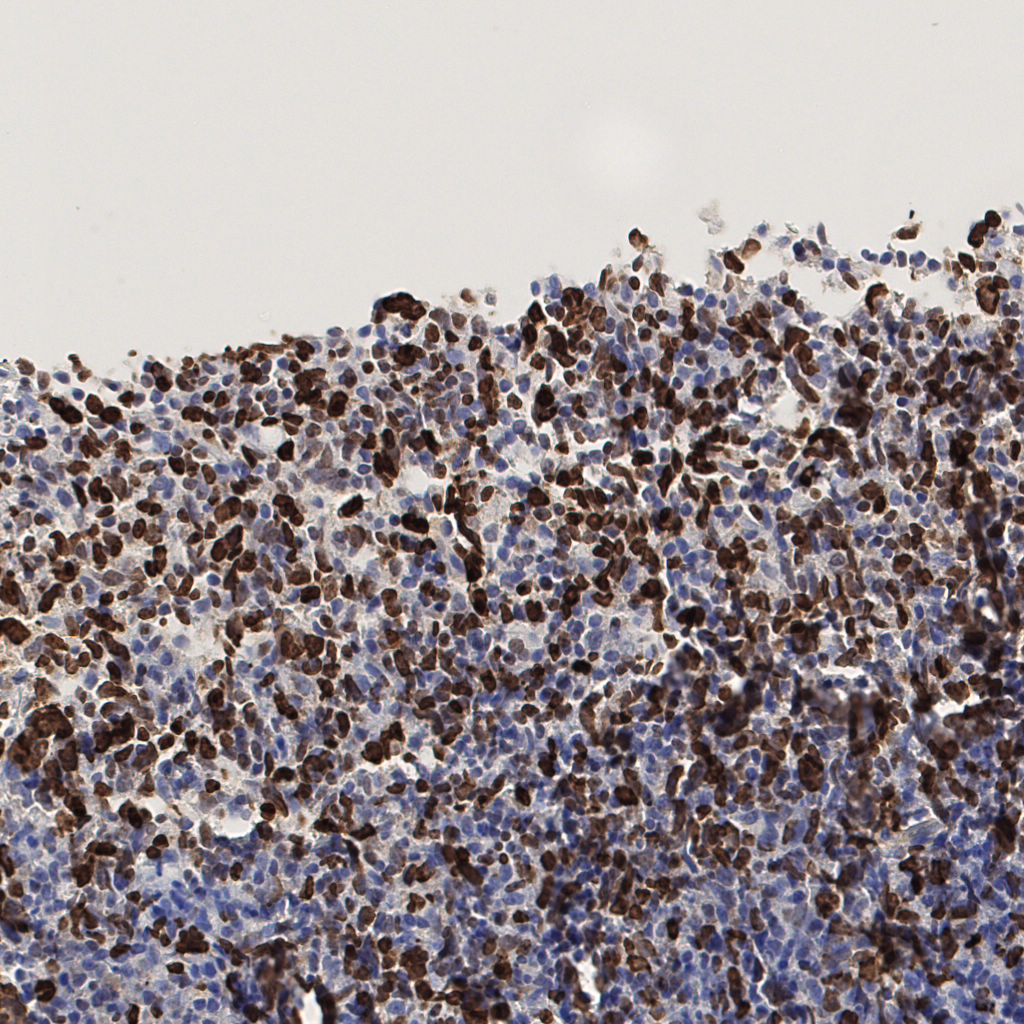

7.85%

Ki67 指数

阴 1104 阳 94

切片统计

总切片 1953

有效 288

已标记 288

有效率 15%